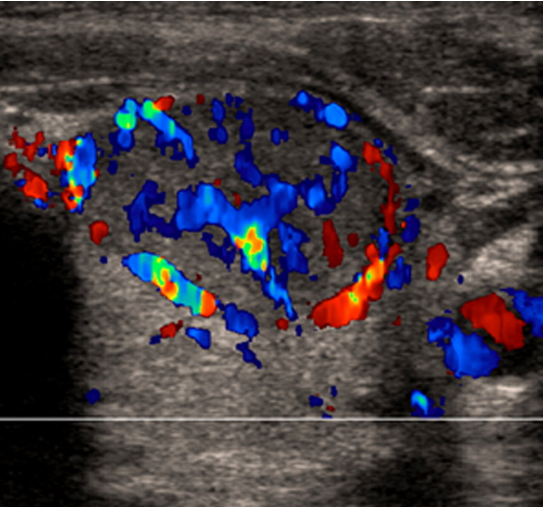

US features of nodules- benign, maligant

-increased vascularity